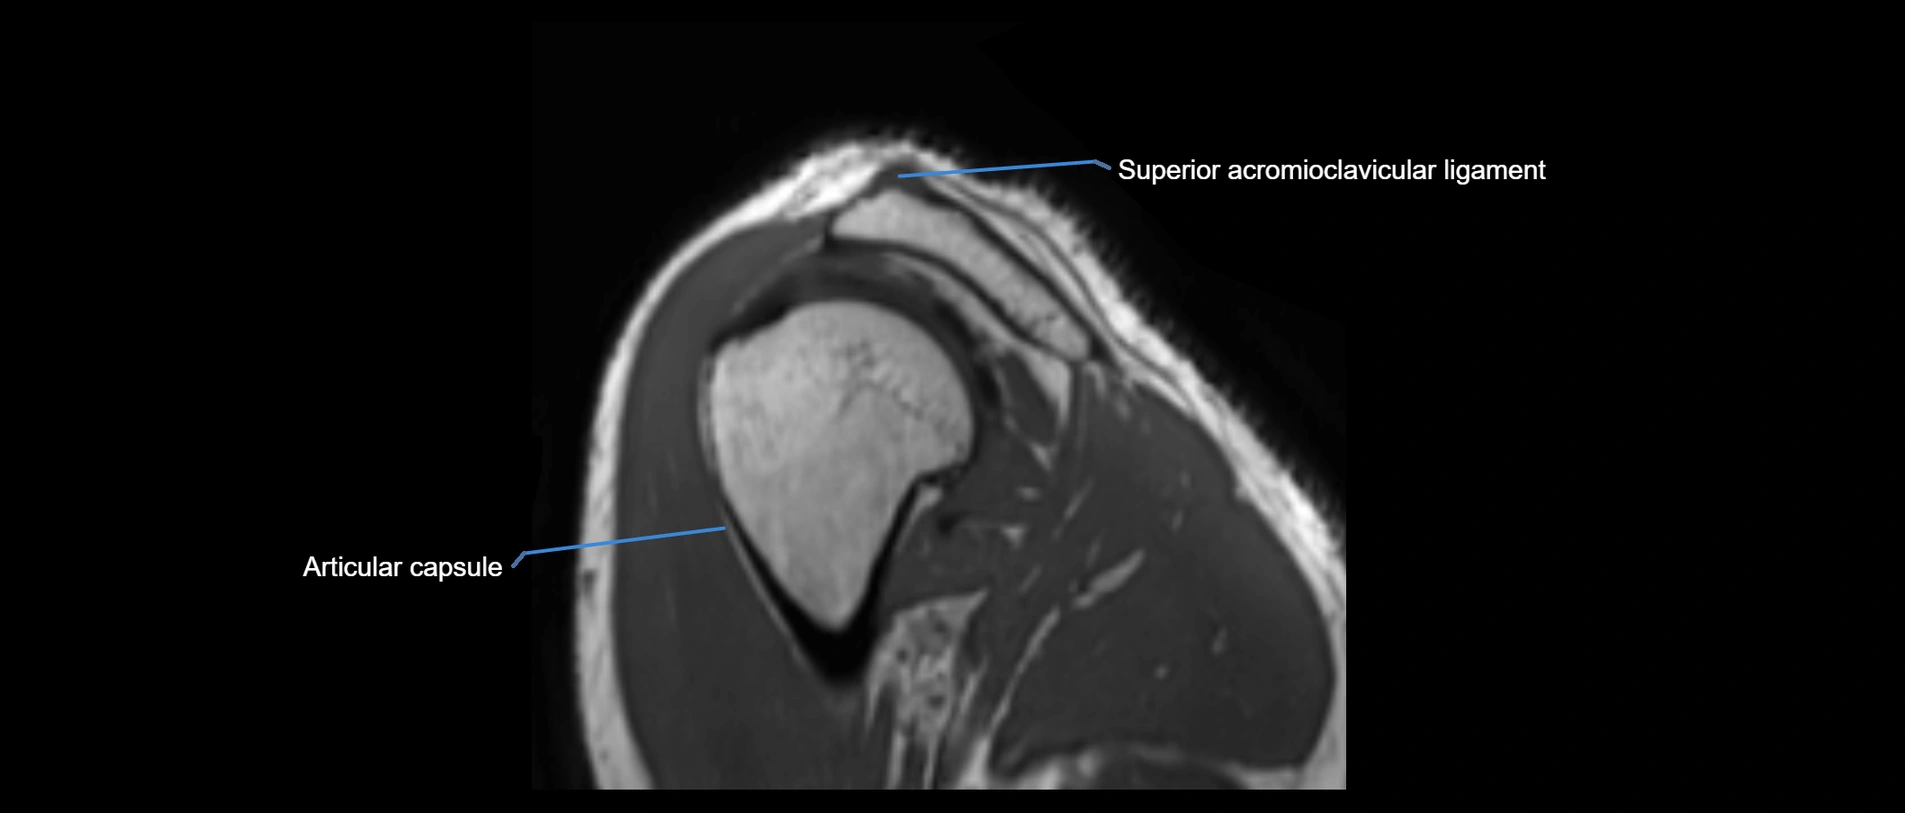

MRI images

image